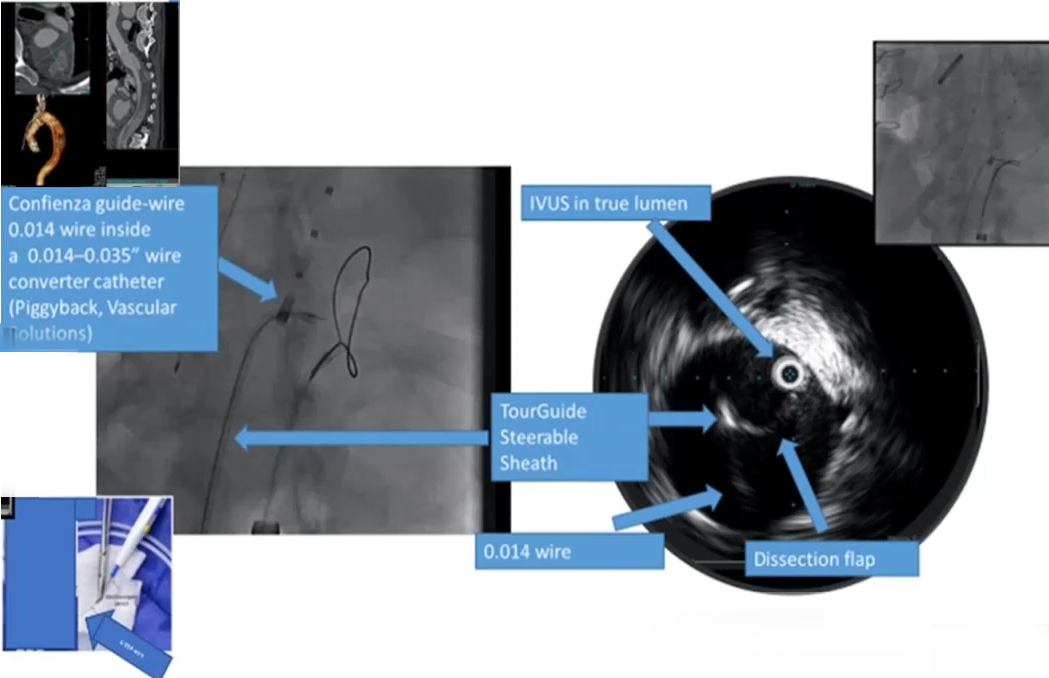

可以通过夹层裂口或者破膜进入假腔放置栓塞材料,并借助术前CTA、影像融合以及IVUS的辅助。

举一个在髂总动脉继发破口处进入假腔的一个例子:

使用IVUS定位导管进入假腔的位置,进行弹簧圈或者血管塞的栓塞,可以将其比作往“假腔里扔垃圾”。

术后CTA也显示“假腔内垃圾”的效果良好,成功堵塞了假腔。同时我们需要注意的是,在这个阶段正确的影像学辅助的重要性。

腔内电灼术不再拉线,而是直接将导丝通电,通过下图看到,可以通过一些导管来保护导丝,以便使内膜片处唯一暴露的导丝打折点通电。在内膜片处切开3cm的切口,然后在IVUS指导下回撤。